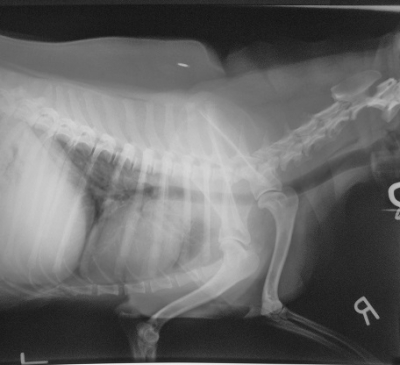

In this X-ray the Canine that was presented was extremely sore.  The Doctor wanted to look at her Spine as well as

her Joints for Arthritis.  As you can see this Dog is also Microchipped!